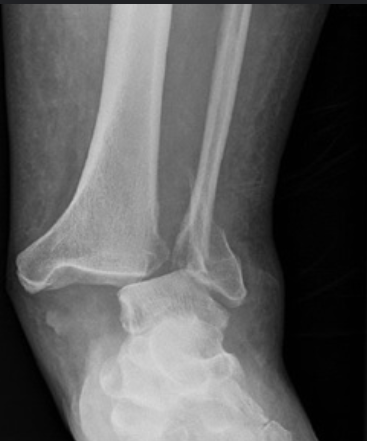

There is more than just a very displaced fracture here. What term must be used when describing this injury?

A

fracture dislocation

Describing as displaced undersells the severity of injury